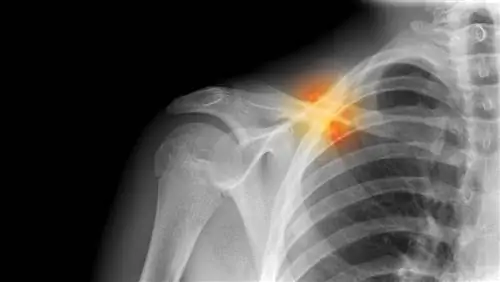

Вывихи: общие вывихи суставов

вывих плеча

Когда две кости, которые соединяются вместе, чтобы сформировать сустав, расходятся, сустав описывается как вывихнутый. Контактные виды спорта, такие как футбол и баскетбол, а также виды спорта с высокой ударной нагрузкой и виды спорта, которые могут привести к чрезмерному растяжению или падению, вызывают большинство вывихов.

Вывихи требуют лечения

Вывих сустава - это неотложная ситуация, требующая лечения. Суставы, наиболее подверженные вывиху, - это суставы рук. Помимо этих суставов, наиболее часто вывихивается плечевой сустав. Вывихи коленей, бедер и локтей встречаются редко.